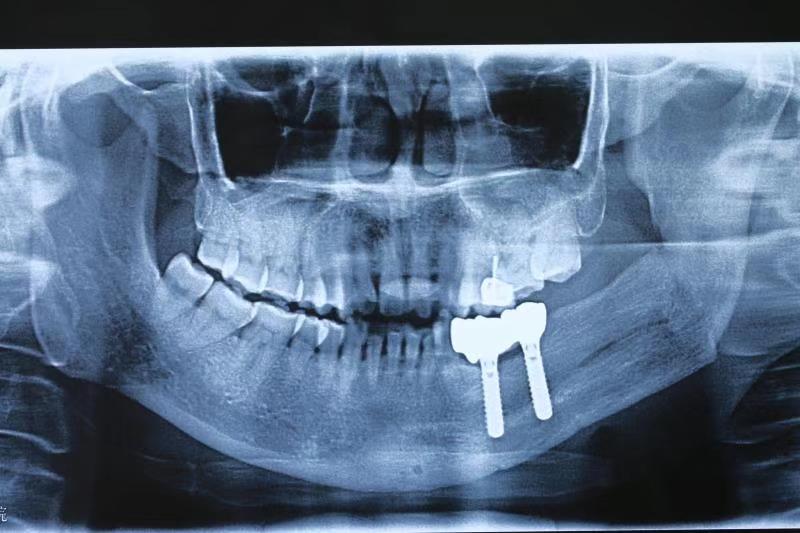

二、针对肿瘤、创伤治疗术后的复杂颌骨、牙列以及软组织缺损,采用种植技术联合骨移植进行功能性重建,尽最大程度恢复患者的咀嚼、发音以及吞咽等口腔功能,提高患者生存质量。(图为下颌骨区段缺损游离腓骨肌皮瓣移植术后行牵引成骨,二期种植行种植修复。